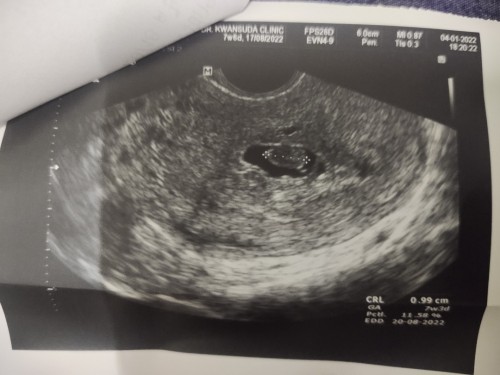

นับจากประจำเดือนเราได้ 9 w ตรวจผ่านช่องคลอดขนาดได้เท่า 6 w (0.48)พบถุง พบตัว แต่ไม่พบหัวใจ หมอนัดอีกที 2 อาทิตย์ หมอบอกอาจเพราะไข่ตกช้า สู้ๆไปด้วยกันนะแม่